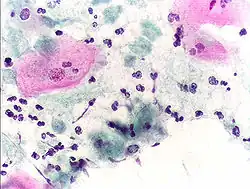

Micrograph of a normal pap smear -

Micrograph of a Pap test showing a low-grade intraepithelial lesion (LSIL) and benign endocervical mucosa. Pap stain. -